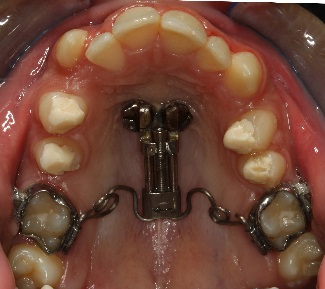

PENDULUM APPLIANCE – PROBLEMS AND POSSIBILITIES IN ITS APPLICATION AT DIFFERENT AGE PERIODS

Статията обсъжда съществували разлика при дистализиране на горни молари, ако пациентите са в различен растежен етап или завършили растежа си, т.е. растящи, млади възрастни и възрастни.